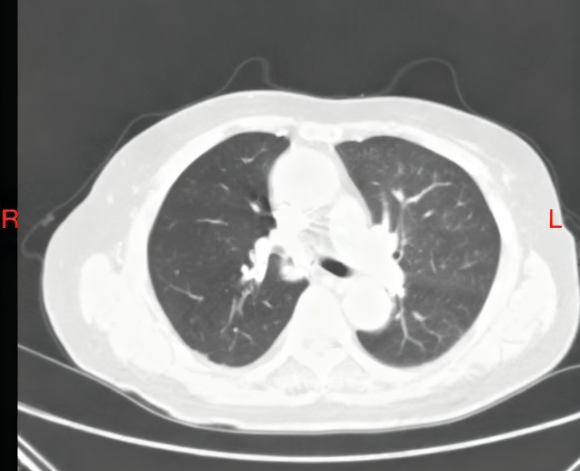

夏奶奶近两年来一直被间断的胸闷、气短、咳嗽、咳痰困扰。半月前,她的病情急剧加重,出现了痰中带血的症状,家人紧急送至东院区。呼吸与危重症医学科阎杰副主任医师接诊后,立即为夏奶奶进行胸部增强CT检查。结果提示“右肺门增大,右肺主支气管内结节状软组织密度灶,右肺下叶不张”,高度怀疑恶性肿瘤。

患者CT检查